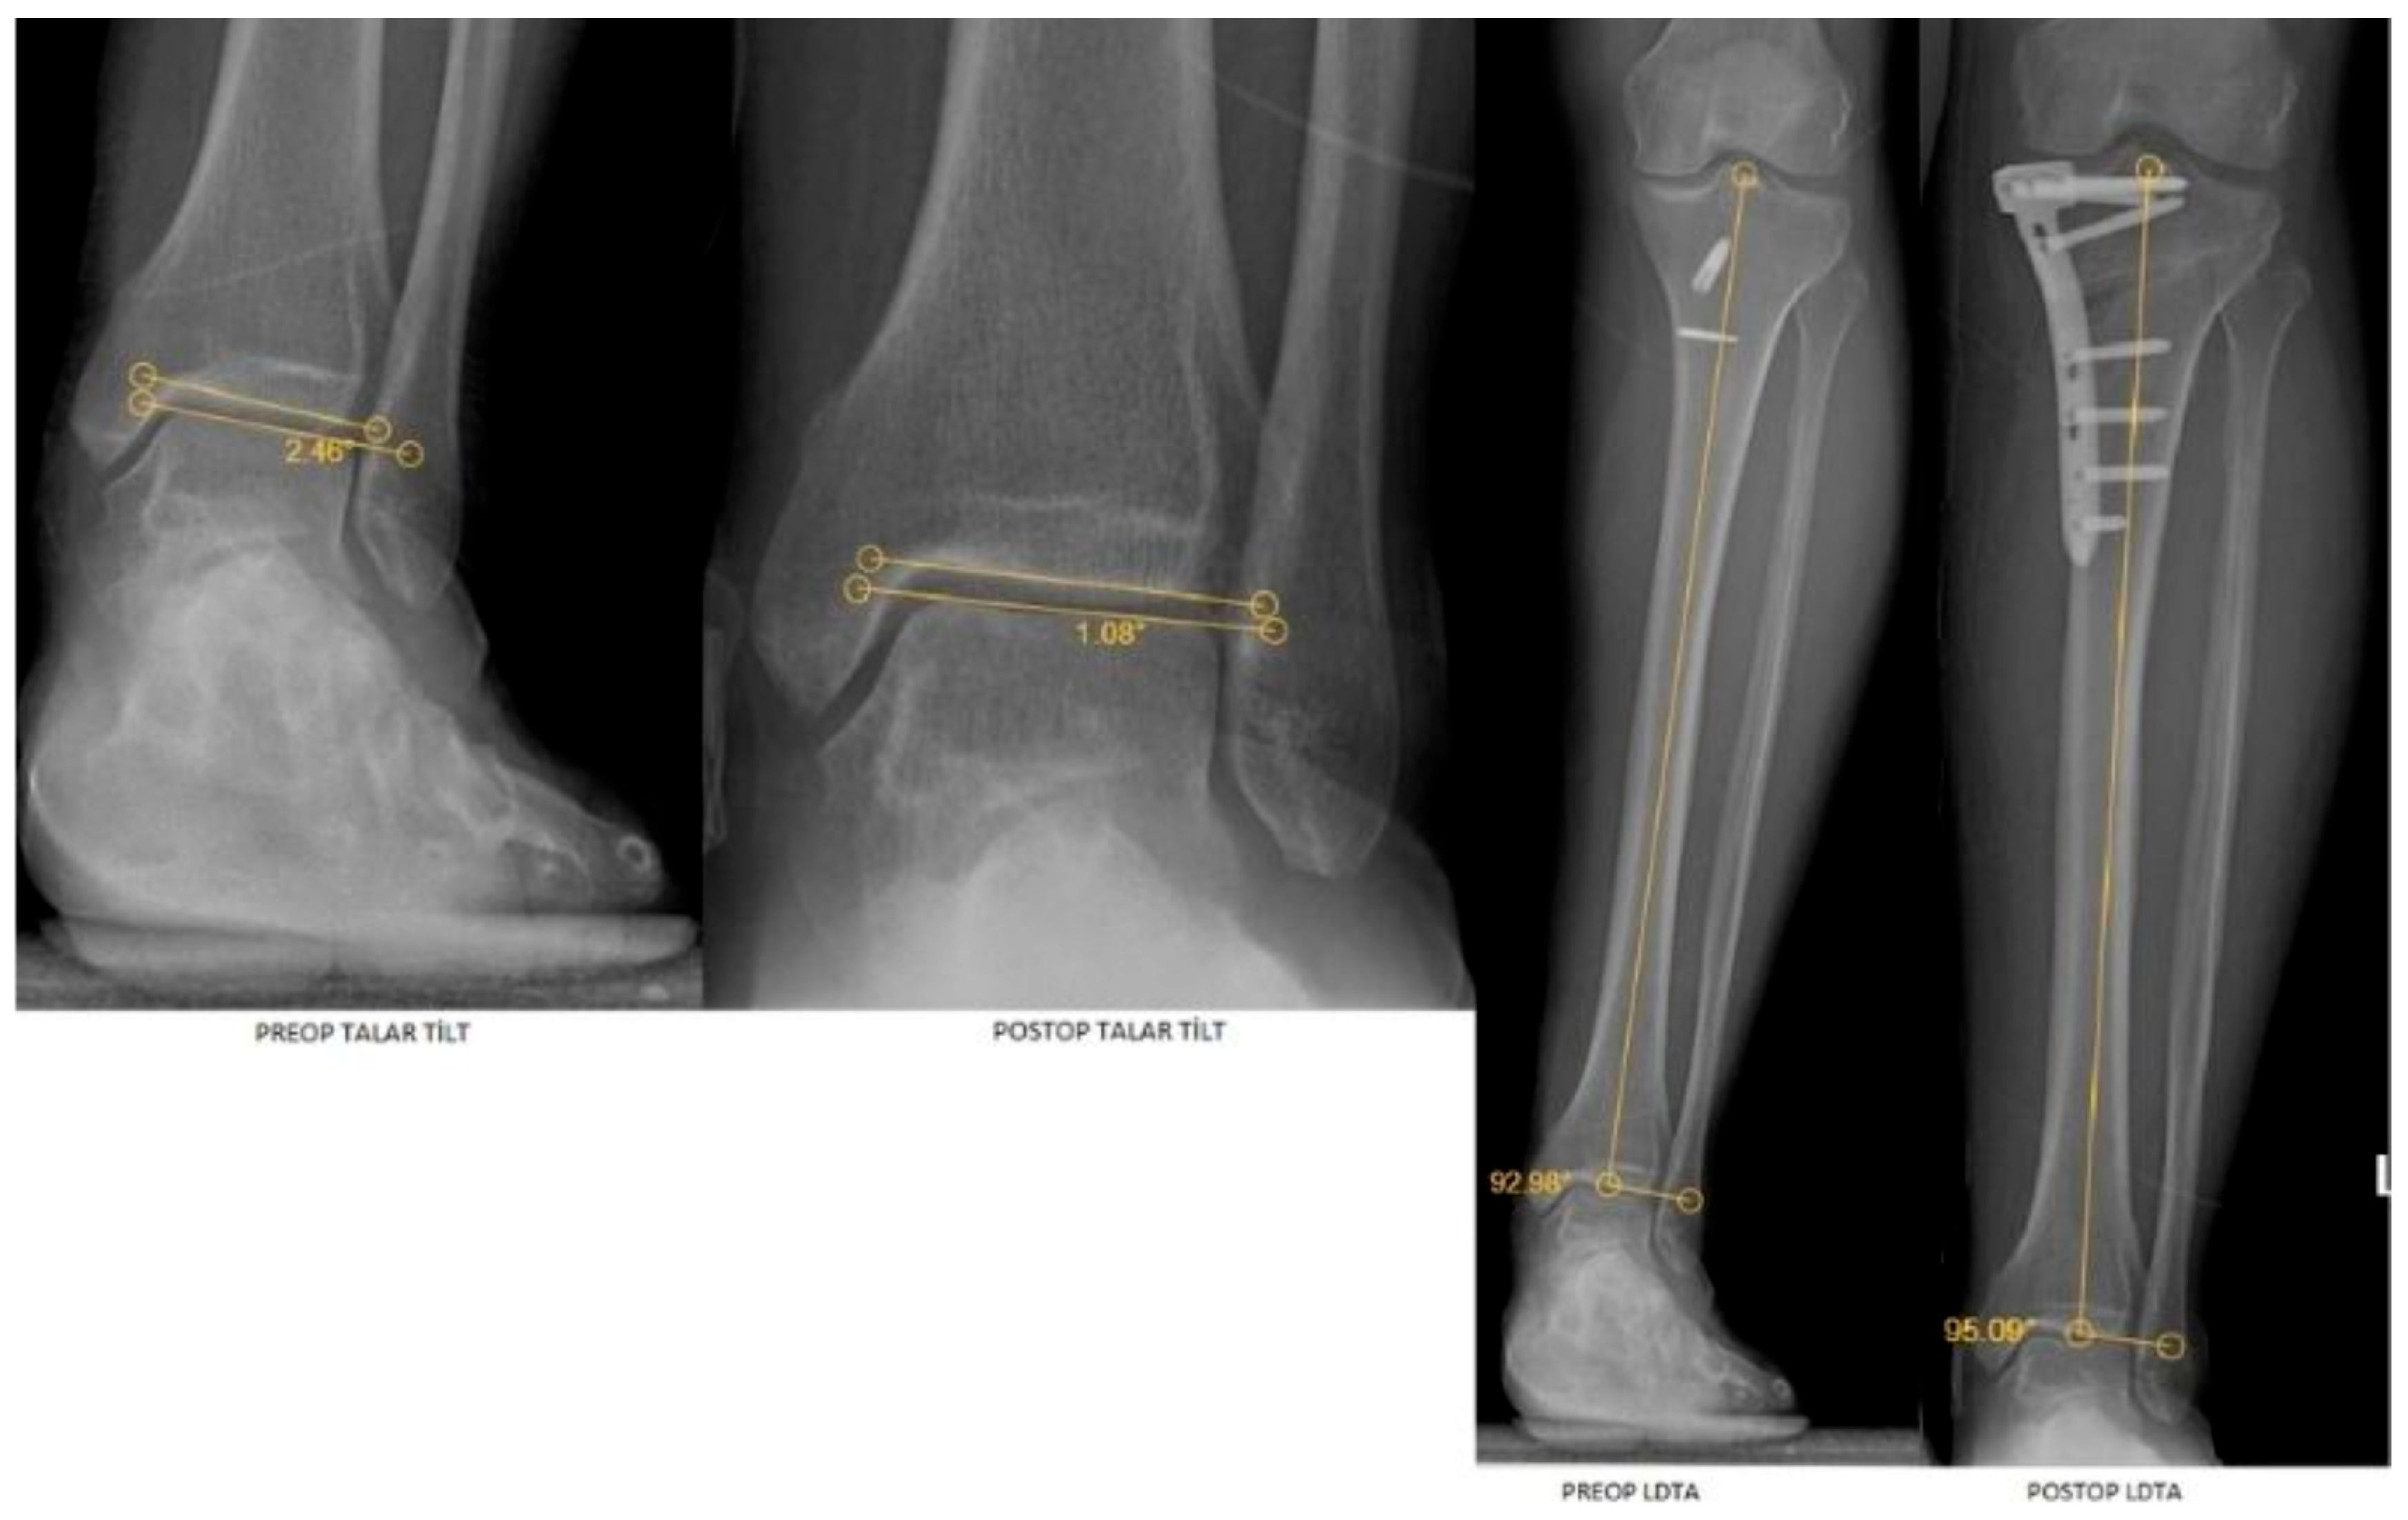

| LDTA | 87.25 (2.76) | 88.14 (2.24) | 0.018 a | 0.225 | 0.690 (0.577–0.776) |

| Talar tilt | 0.85 (0.51) | 0.70 (0.52) | <0.001 a | 0.752 | 0.863 (0.806–0.904) |